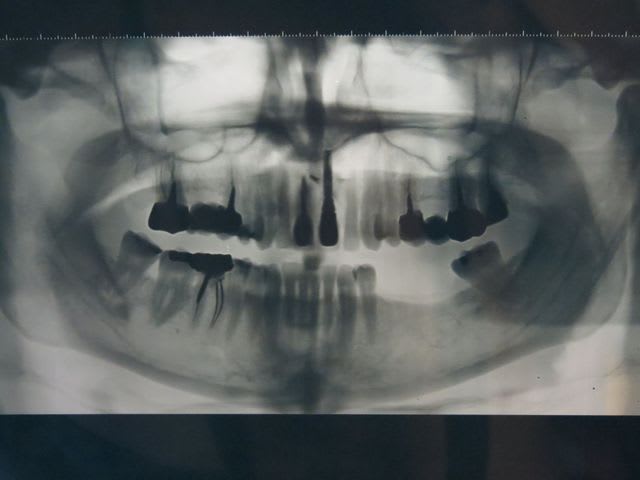

patiente de 49 ans caucasienne, fumeuse 1 paquet/jour depuis ses 18 ans, nerveuse, déficit en protéine S.

Antécédent de grosse infection/extraction/comblement sur 21

1ère fois que je la vois, bilan pano, je bloque d'abord sur l'image radioclaire suspecte à l'apex de 46 et 47, même genre d'image autour de l'apex de 48, et en y regardant de plus près, peut être le même d'image également secteur 3, avec les bords du canal dentaire qui disparaissent. Pas de douleur, 47-48 vivantes. Pas de résorption radiculaires, RAS à la palpation.

Je pense à un angiome ou ? J'ai fait faire un scanner. Et ensuite stomato ?

J'aurai fait une rétro argentique sur chaque dent..et pi courrier pour avis au chir buccale du coin, avant de demander un scanner..mais why not!

Pourquoi un angiome? Tu veux dire une tumeur osseuse?

Perso je pense que c'est sûrement endo, vu les obtu profondes..